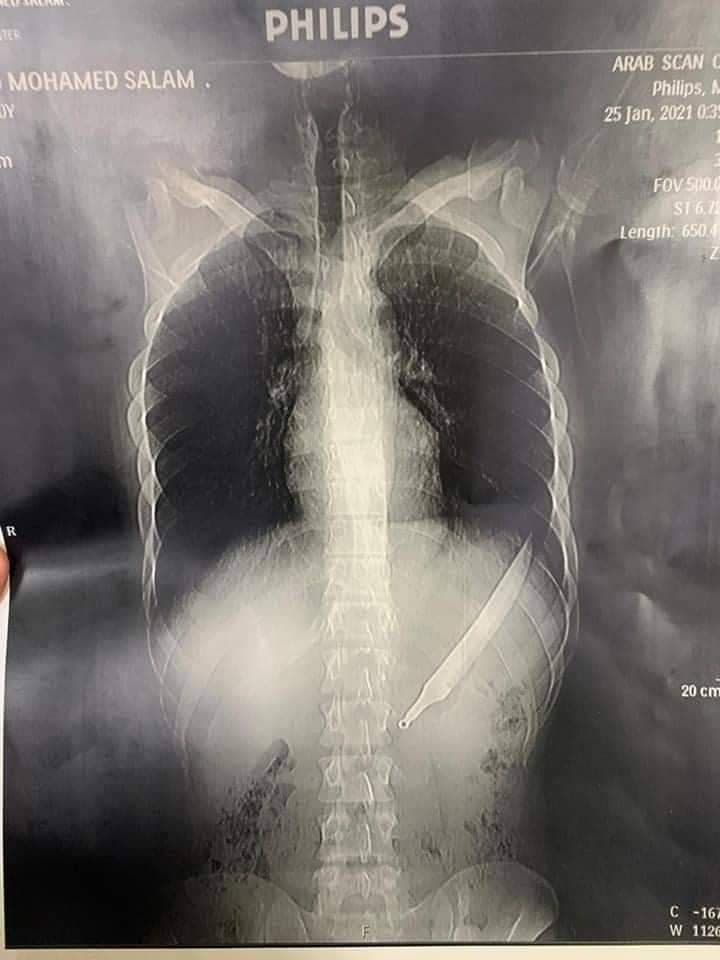

نجح فريق من اطباء الدقهليه اليوم الاربعاء 27 يناير 2021 في انقاذ حياه شاب ابتلع سكين مطبخ وكادت تودي بحياته.

وقال الدكتور سعد مكي وكيل وزارة الصحة بالدقهلية، إن فريق طبي تمكن من إنقاذ حياة مريض ابتلع سكين مطبخ كبير، حيث حضر المريض للمستشفى الدولي يعاني من آلام شديدة بالبطن، وبعمل الأشعات والفحوصات تبين وجود جسم غريب ببطن المريض، وكان يجب عمل استكشاف جراحي فورًا لإنقاذ حياة المريض.

وتم عمل الجراحة اللازمة في الوقت المناسب والحالة الصحية للمواطن مستقرة.